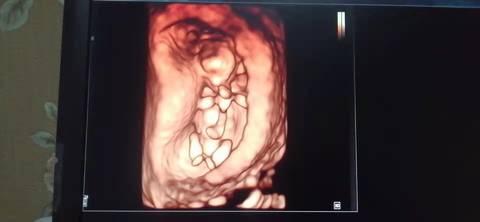

十二周的nt,是不是小棉袄啊? 医生给看宝宝腿的时候生殖器那里是平平的,是女宝吗?我和老公都挺想要小棉袄的

journal_insert_pic_1741079597journal_insert_pic_1741080026journal_insert_pic_1741080197journal_insert_pic_1741080337